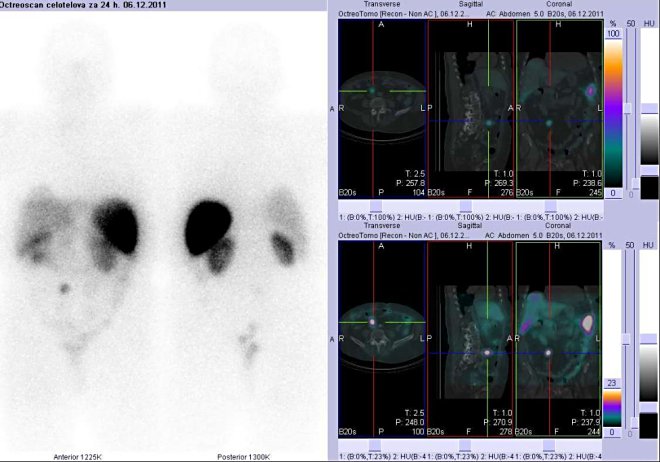

/ Obr. č. 4: Celotělová scintigrafie v přední a zadní projekci a fúze obrazů SPECT a

CT.

Vyšetření 24 hod. po aplikaci radioindikátoru. Zaměřeno na ložisko v levém jaterním laloku.

/

Pozorujeme dvě ložiska patologicky vyšší depozice radioaktivity.

První ložisko je lokalizováno v levém jaterním laloku a druhé v oblasti břicha v pravém mesogastriu. Zřejmě se jedná o lymfatickou uzlinu.

Závěr: dvě patologická ložiska v popsaných lokalizacích se zvýšenou denzitou somatostatinových receptorů odpovídají tumoroznímu postižení při základní dg karcinoidu céka.